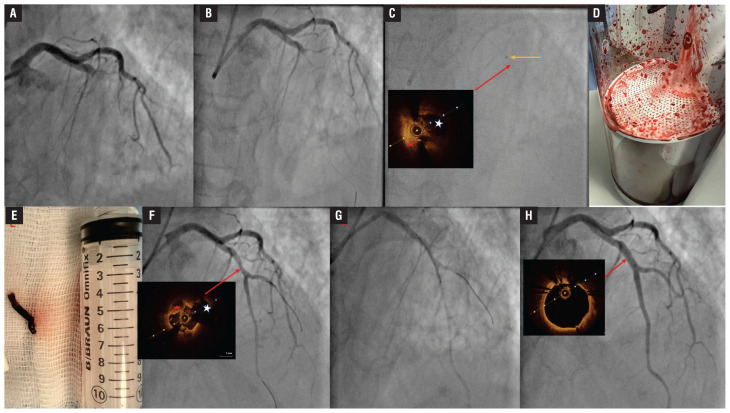

Continuous mechanical aspiration thrombectomy for STEMI with high thrombus burden.